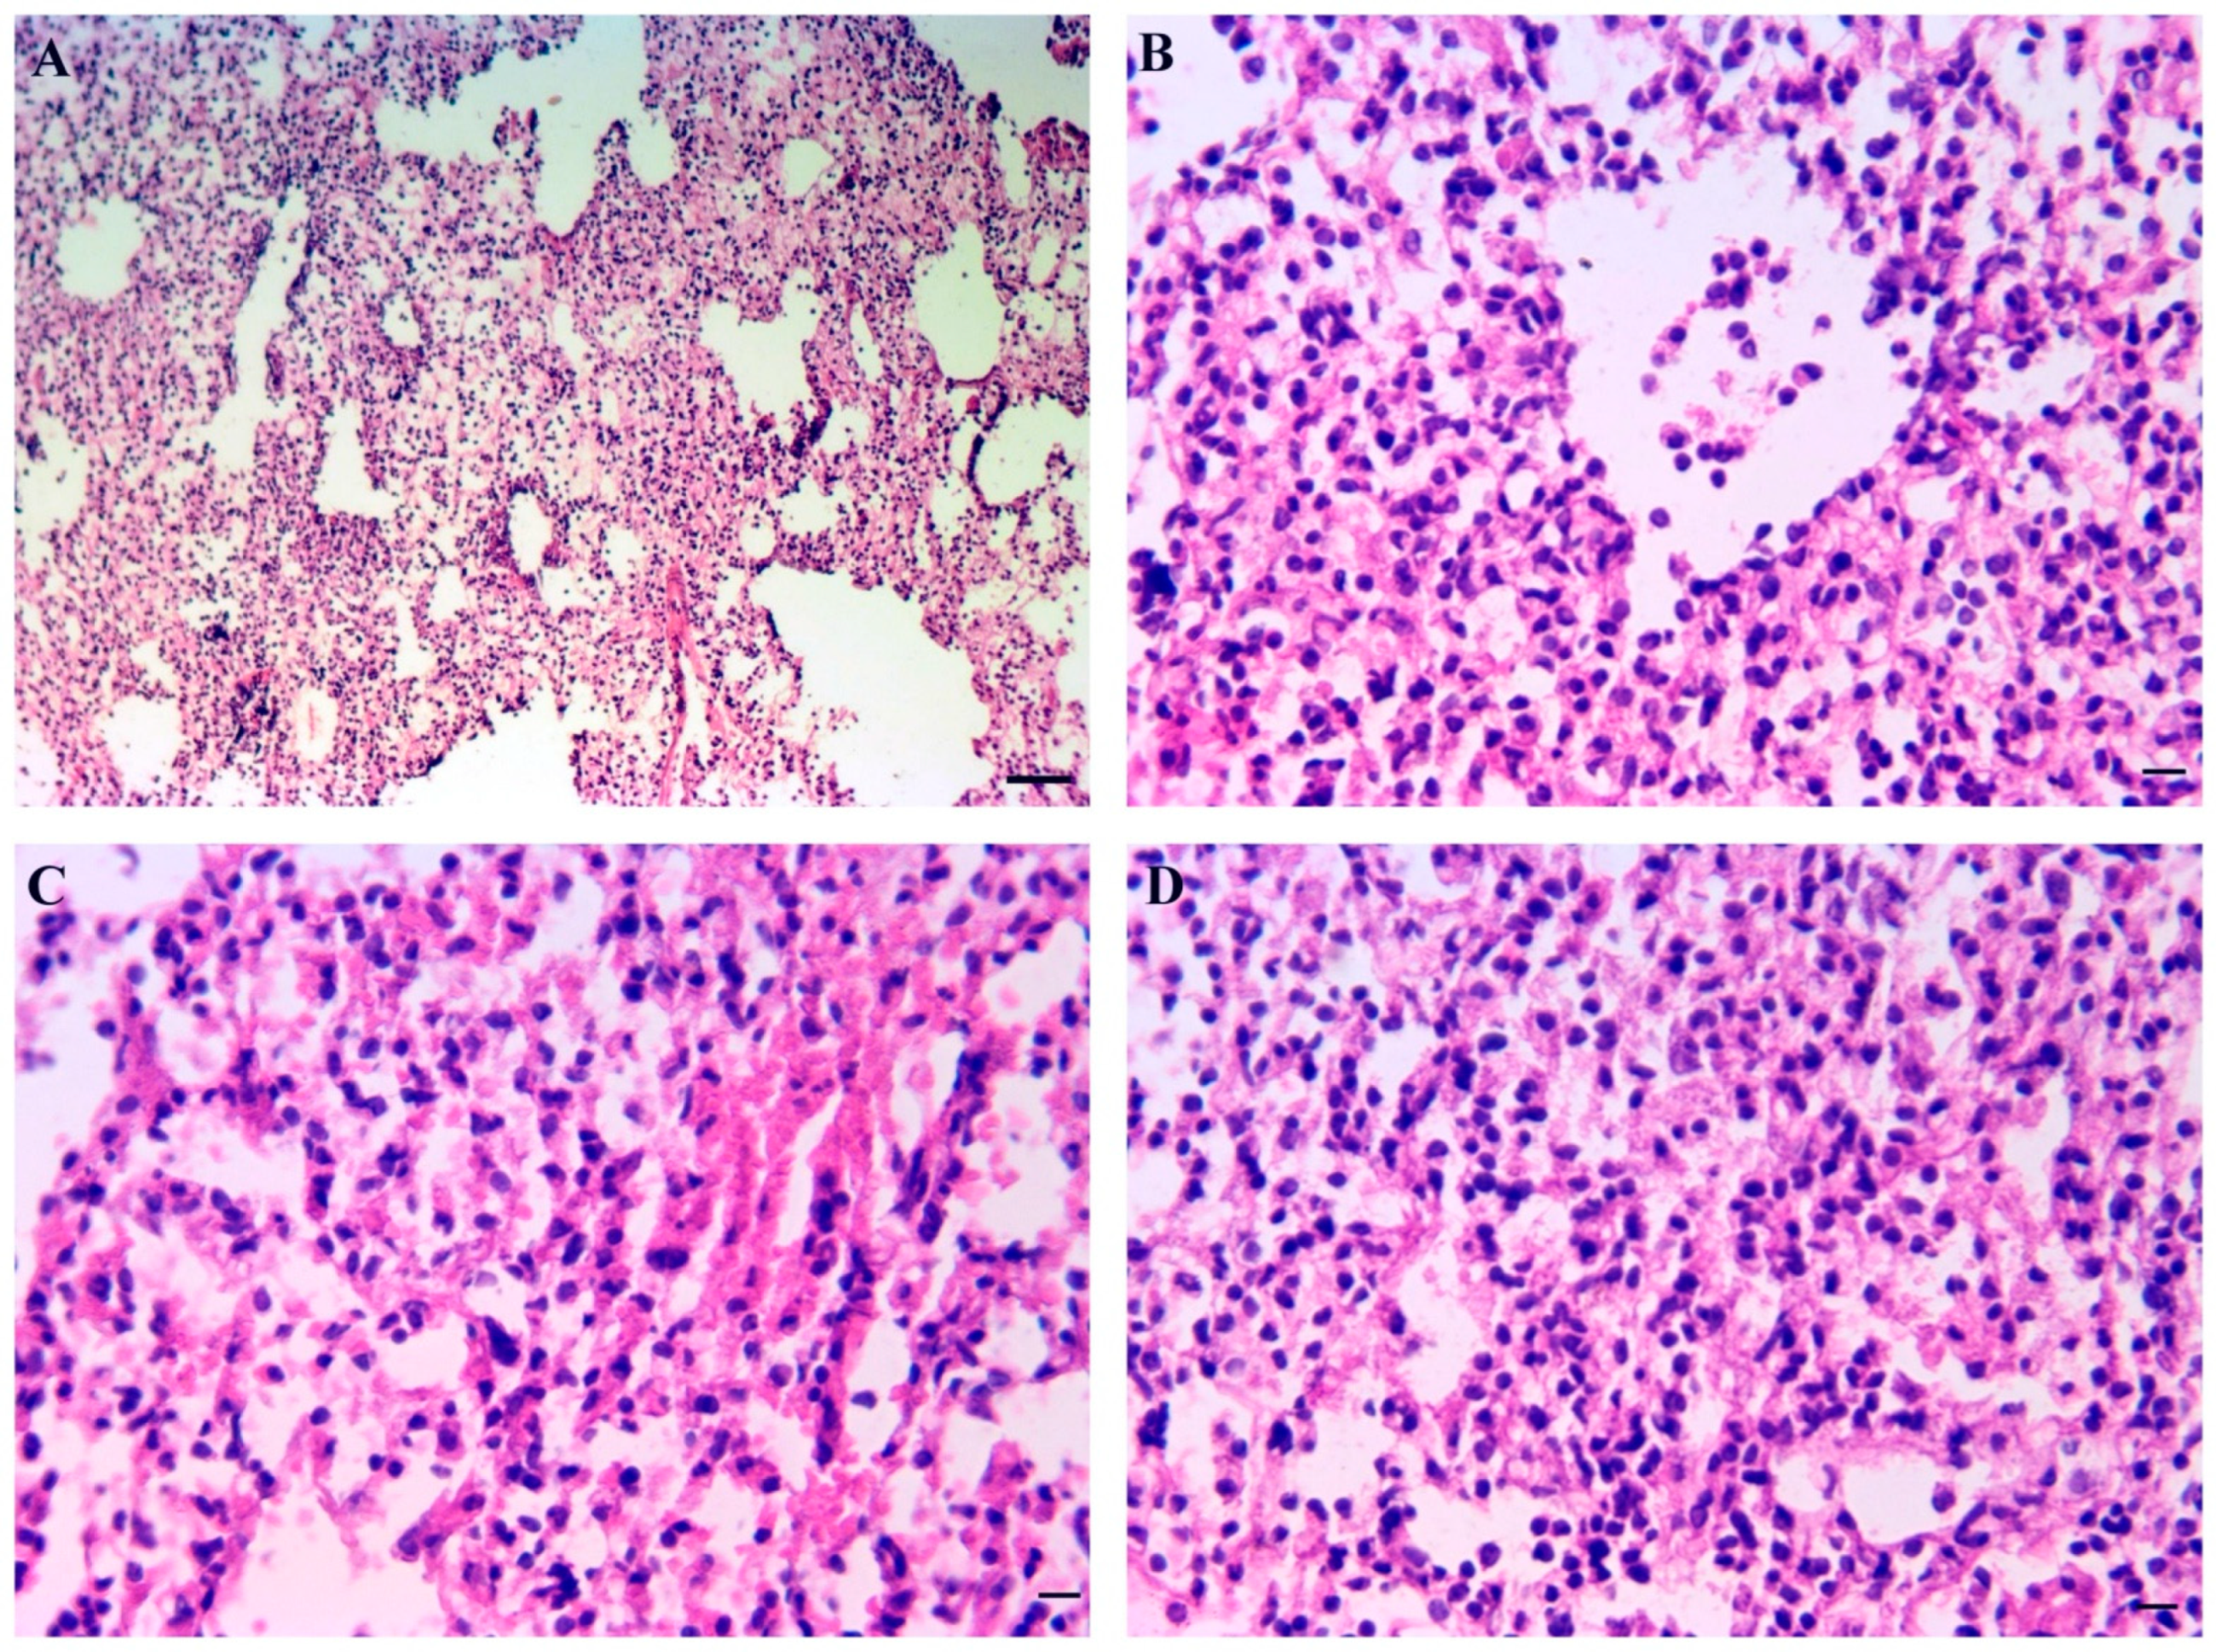

3.9. Inner Organs Histopathology